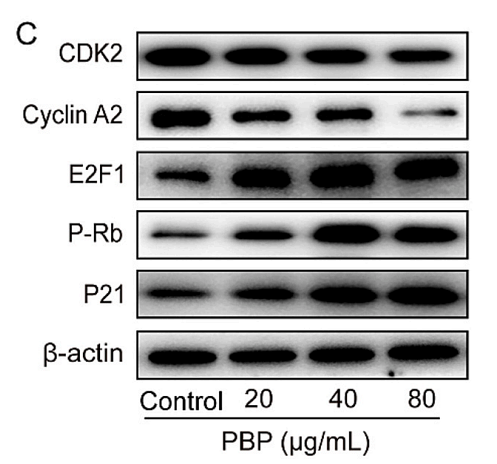

Elucidation of the anti-colon cancer mechanism of Phellinus baumii polyphenol by an integrative approach of network pharmacology and experimental verification

Author:

PMID: 37838121

期刊: International Journal Of Biological Macromolecules

应用: WB

反应种属: Human

发表时间: 2023 Oct

-